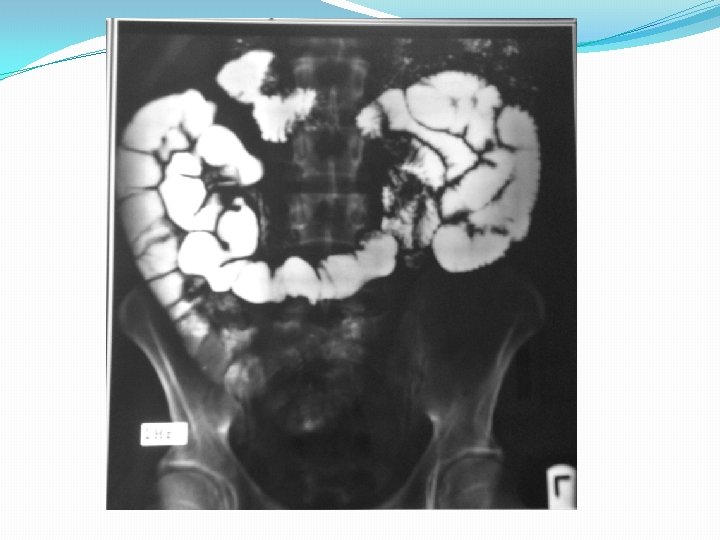

Barium studies of the gastrointestinal tract may suggest the diagnosis but are neither sensitive nor specific. They typically reveal thickening or nodularity in the antrum and a thickened or "sawtooth" mucosa in the small bowel.